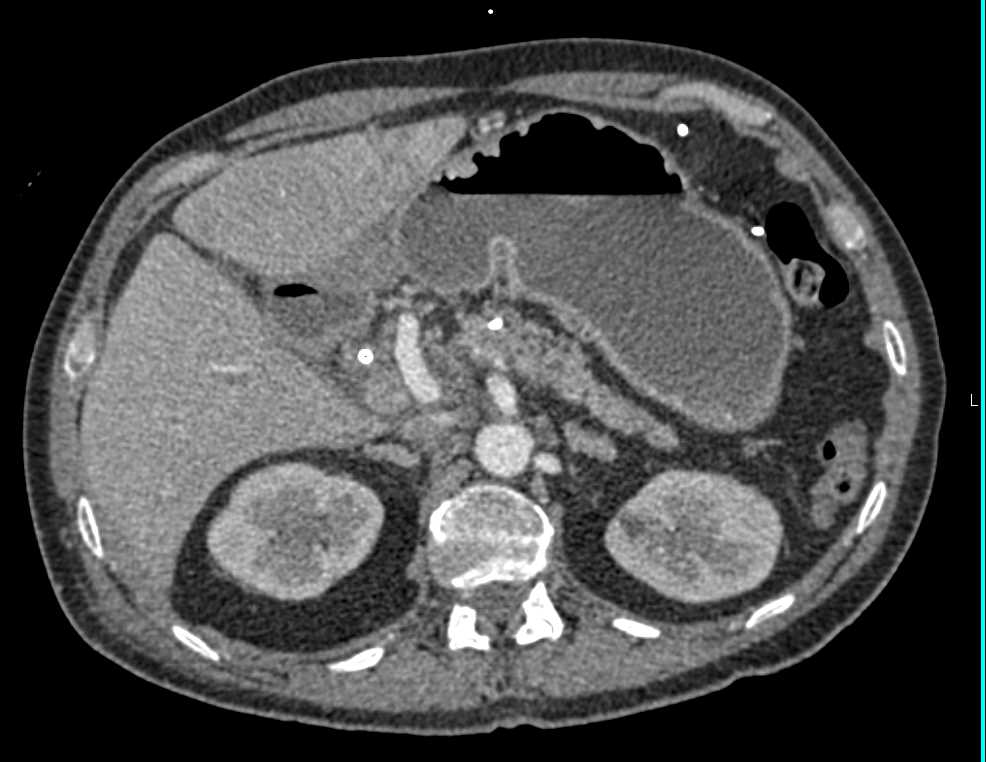

Metastatic Melanoma to Adrenal, Pancreas and Adenopathy